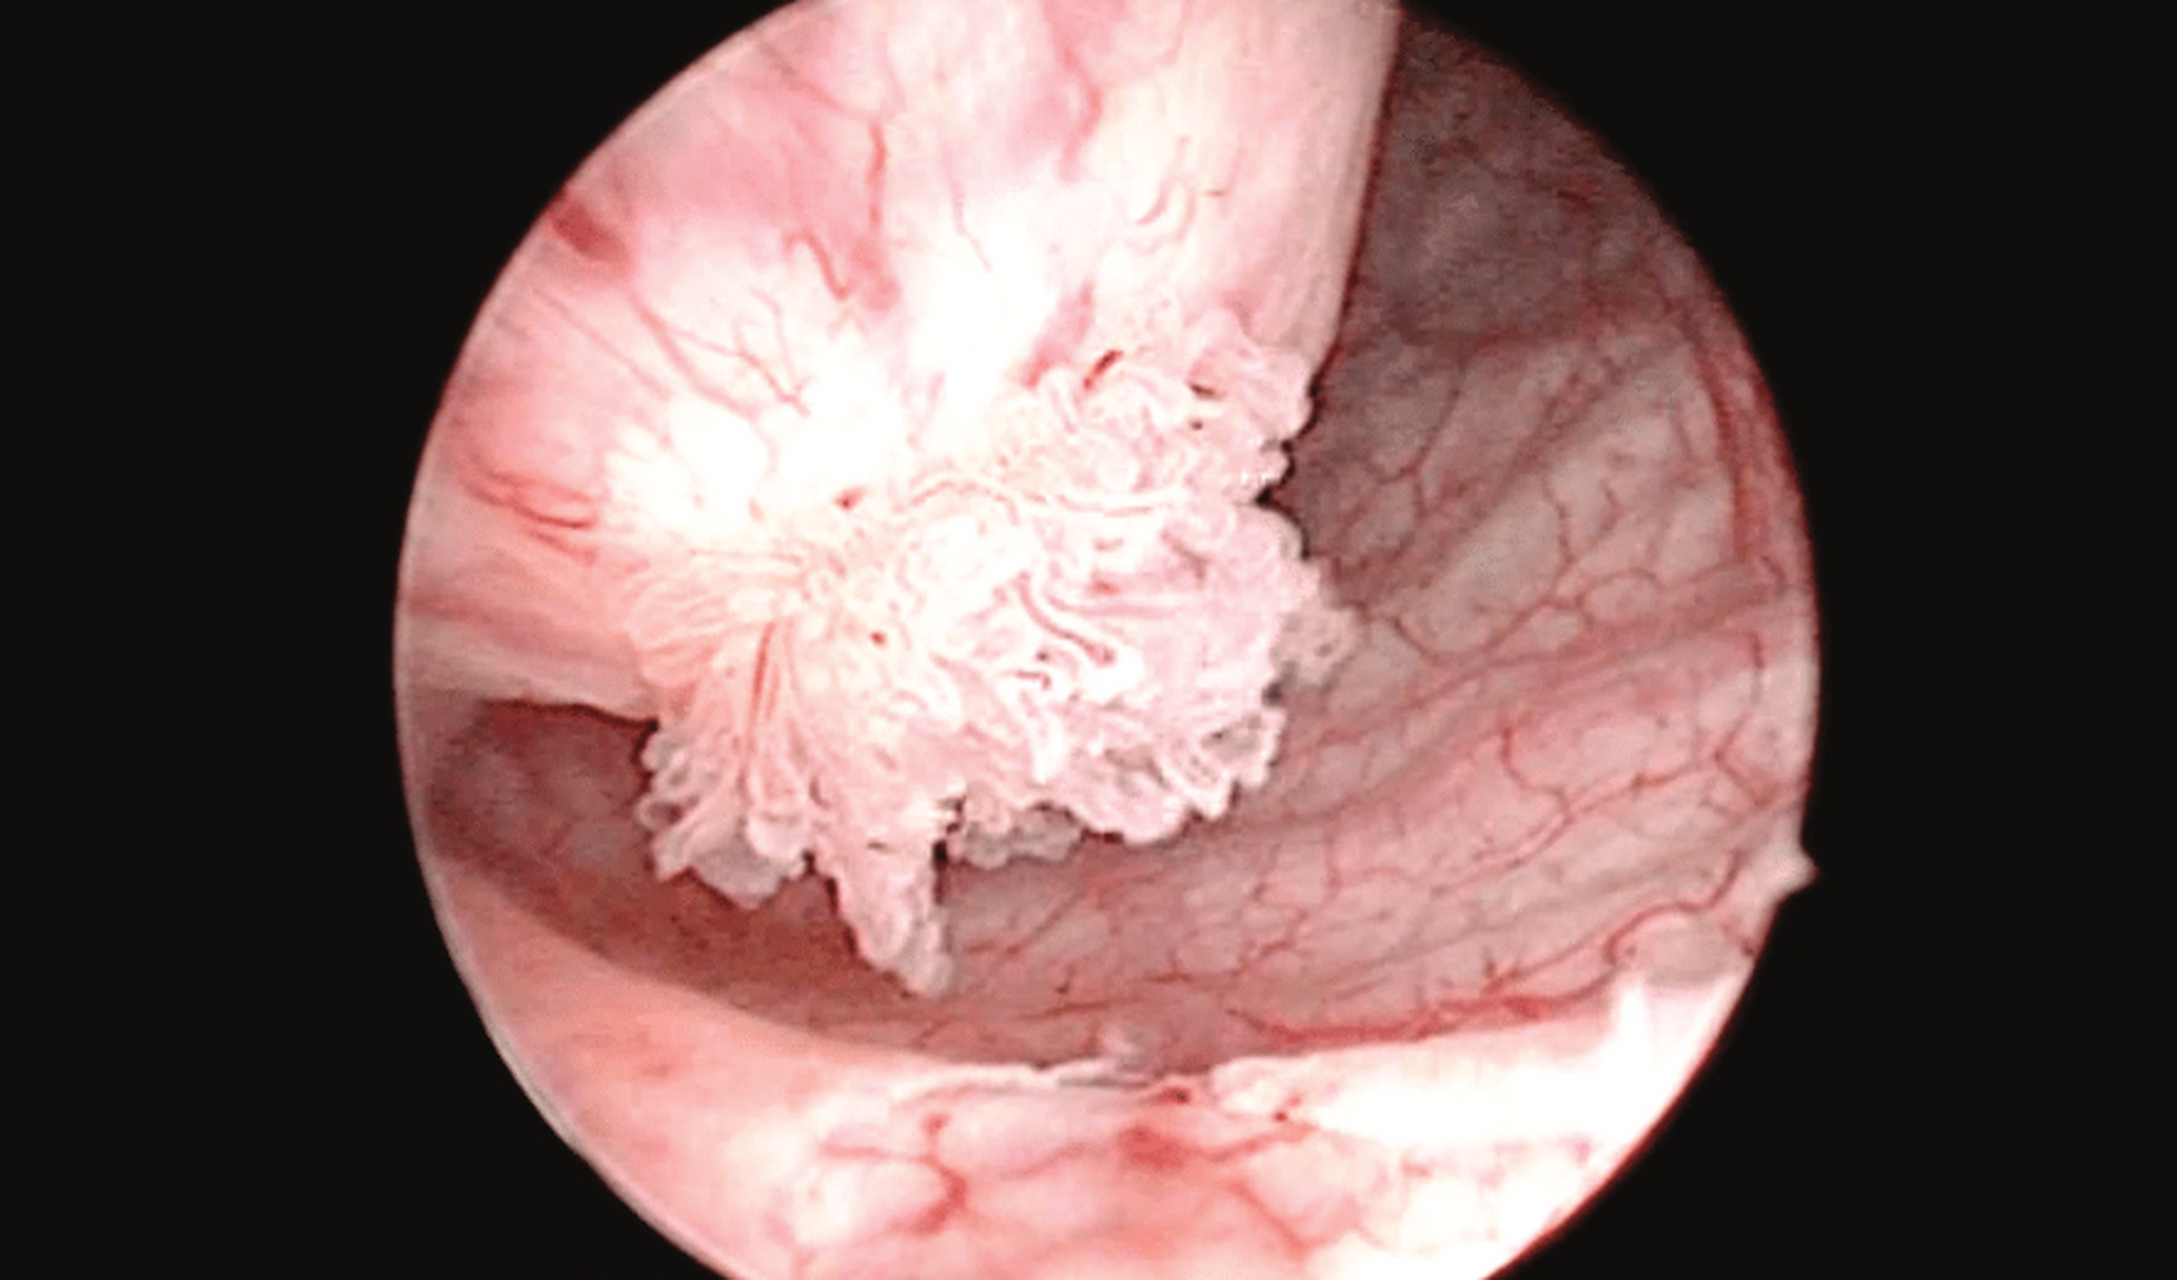

朱医生告诉你 尖锐湿疣,尤其是男性尿道口的尖锐湿疣,通常发生在没有

而尖锐湿疣感染男性后的症状表现男性尖锐湿疣,多出现在尿道口上,在